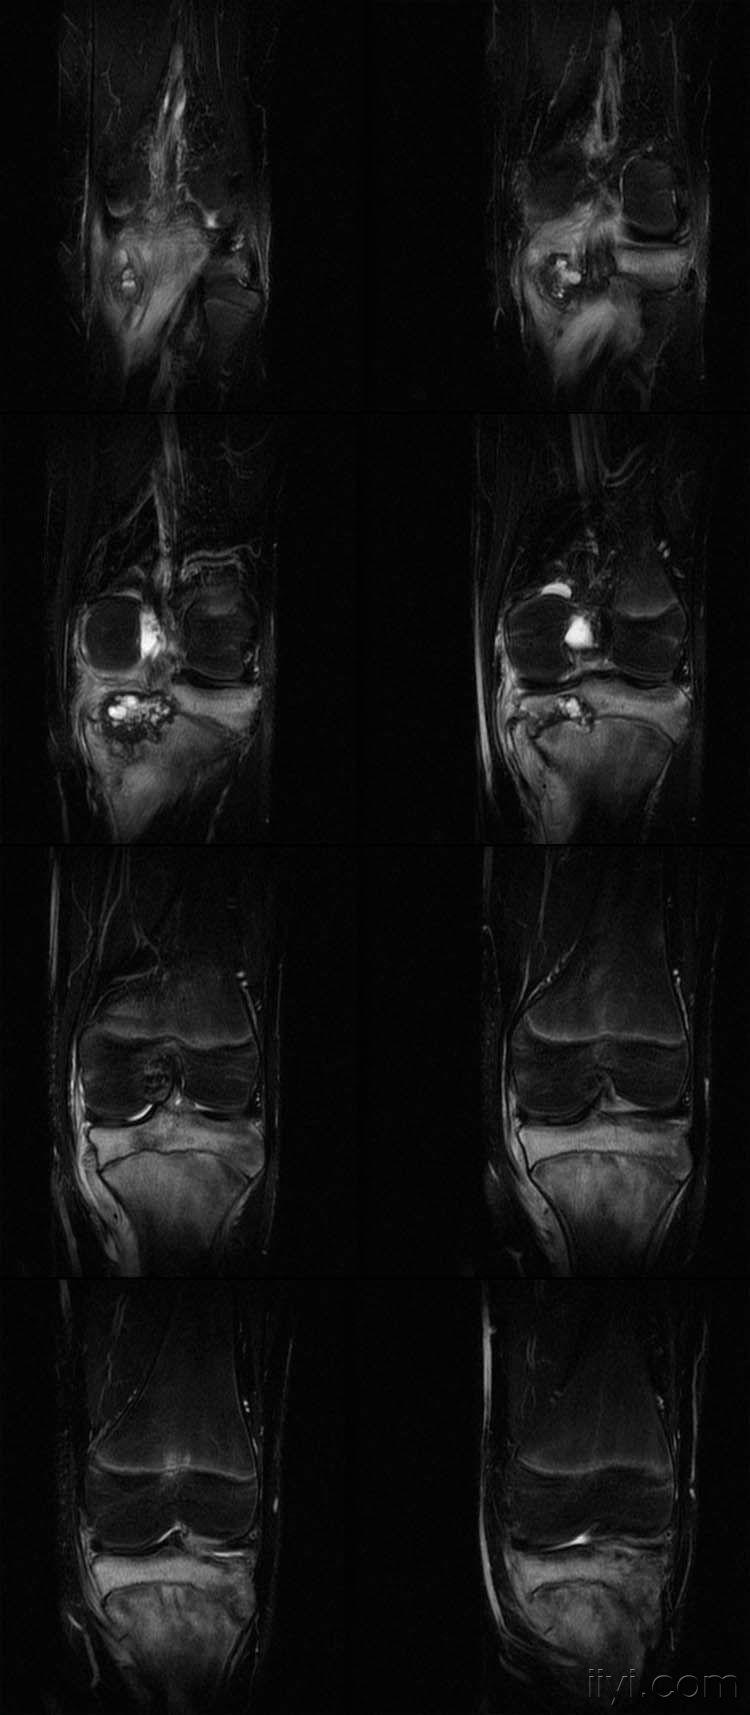

女,14岁,膝关节外伤后疼痛4月余。

向老师学习,恶性肿瘤可能,骨肉瘤?